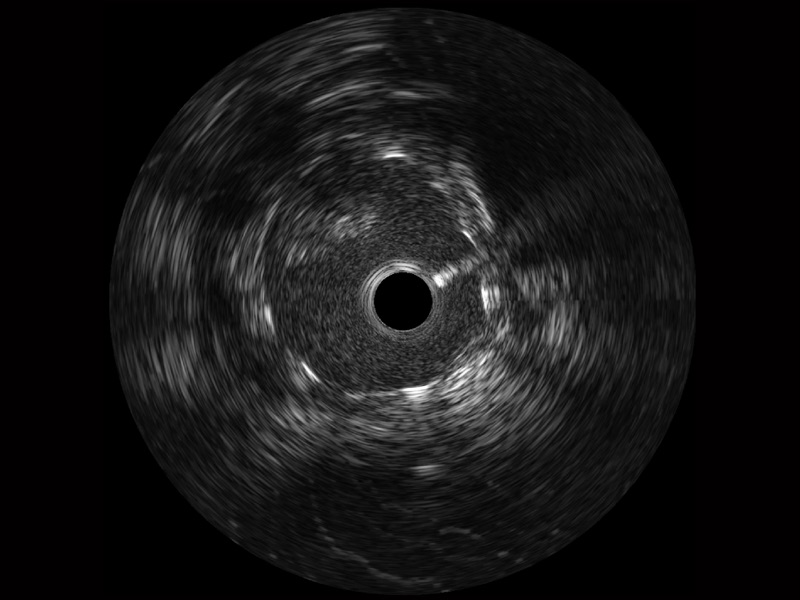

• 传统IVUS图像

对比传统IVUS导管成像,1xBET宽频IVUS图像的近场支架梁显影更细腻,远场中膜外血管仍清晰可辨,兼顾远中近,兼顾分辨力与穿透深度